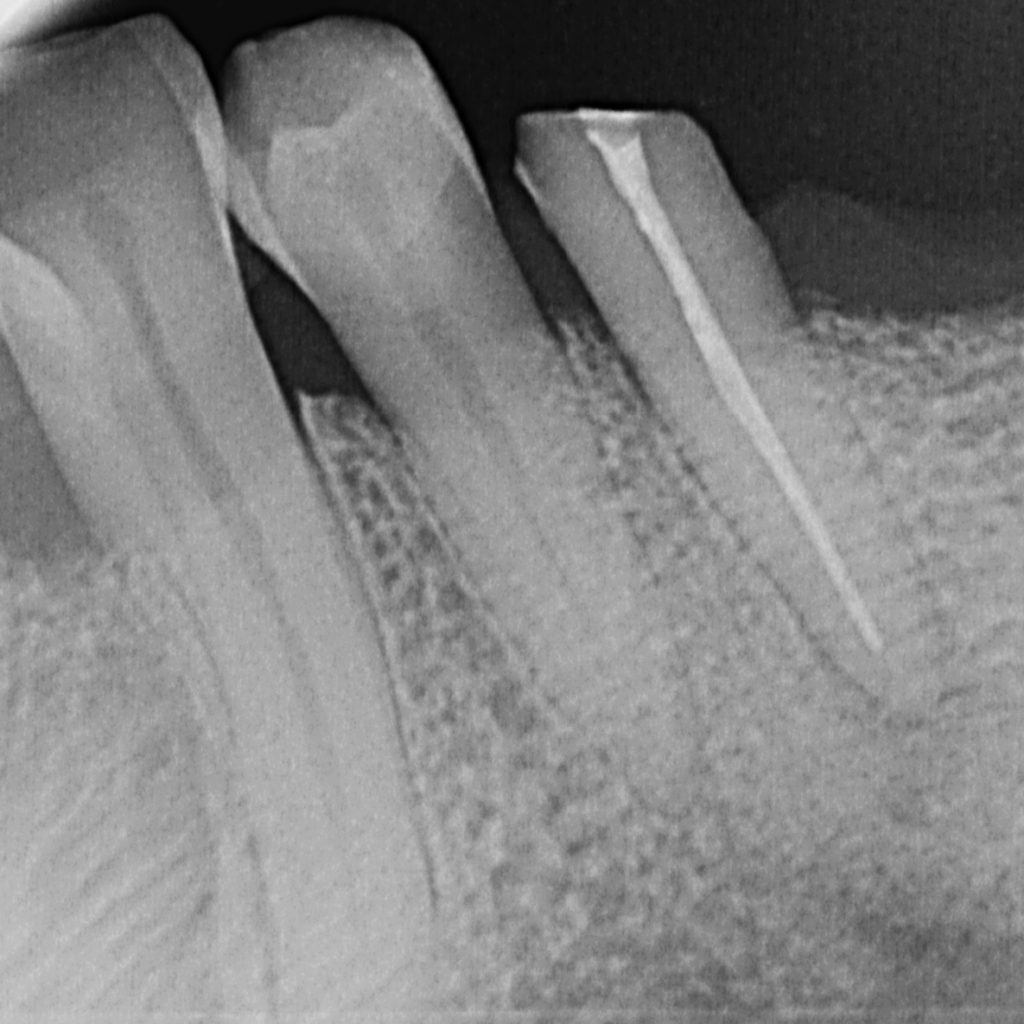

Eine der wichtigsten Untersuchungsmethoden des Zahnarztes ist schon seit Jahrzehnten das Röntgen. Das entstehende Röntgenbild zeigt die innere Beschaffenheit der Zähnen und der Kiefer. Es hilft somit bei der Erstellung von Diagnosen und ist für die Behandlungsplanung eine wichtige Voraussetzung. Je nach Fragestellung kann ein digitales Röntgen von einzelnen Zähnen und begrenzten Kieferbereichen, aber auch eine umfassende, so genannte Panoramaaufnahme (ein OPG) angefertigt werden.

Das Erstellen einer Röntgenbildes dient beispielsweise der Diagnose von Erkrankungen des Zahnhalteapparates, Frakturen von Zahn und Kiefer, Entzündungen, Neoplasien, der frühzeitigen Erkennung von Nichtanlagen, verlagerten und retinierten Zähnen sowie der Erkennung von Karies. Da in vielen Fällen die Oberfläche der Zähne glatt ist und der Zahnschmelz auf den ersten Blick intakt scheint, ist ein Teil der beginnenden Karies für den Zahnarzt nur im Röntgenbild erkennbar.